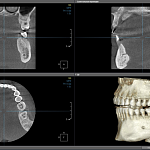

КТ Компьютерная томография челюстно-лицевой области

Компьютерная томография (КТ)

Современный метод диагностики, который создает детальное трехмерное изображение ваших зубов

Наш КТ-аппарат обладает областью исследования 15×10 см, что позволяет проводить максимально точную и информативную диагностику.